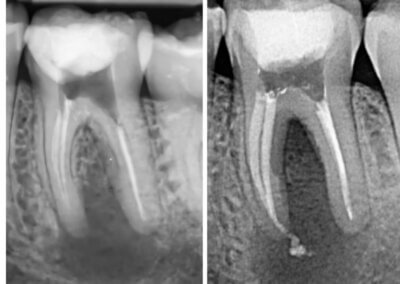

Endodonția este o ramură esențială a stomatologiei, axată pe diagnosticarea, prevenirea și tratamentul afecțiunilor pulpei dentare și a țesuturilor periapicale. Această specialitate joacă un rol crucial în salvarea dinților naturali, evitând extracțiile și menținând sănătatea orală pe termen lung. Prin tehnici avansate și echipamente de ultimă generație, endodonția asigură tratamente precise și eficiente, contribuind la redarea sănătății și funcționalității dinților într-un mod durabil și predictibil.

Utilizarea tehnicilor moderne asigură un tratament rapid, precis și confortabil pentru pacient.

Reconstituirea coronară cu materiale de calitate conferă rezistență pe termen lung.